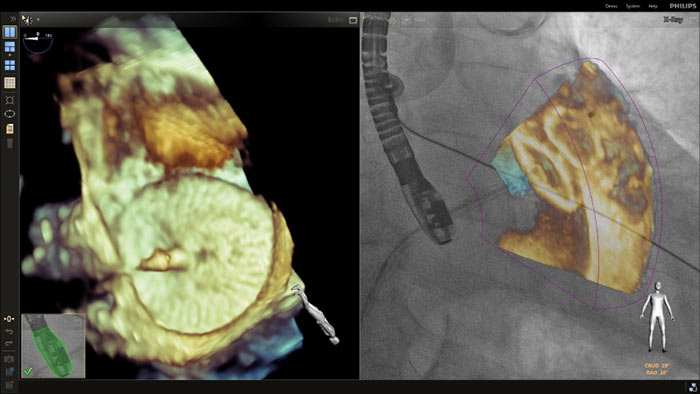

En el centro de nuestra suite, la exclusiva solución EchoNavigator es el ejemplo emblemático del compromiso de Philips con la multimodalidad y la integración del flujo de trabajo, aporta lo mejor de ambos mundos del líder de la industria en soluciones cardíacas intervencionistas de rayos X y ecografía.

Implementación de la superposición de la ETE 3D en vivo de la oclusión de la LAA con EchoNavigator

Guía de punción transeptal mediante EchoNavigator